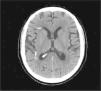

Hallazgos de imagenLas imágenes de TC muestran la presencia de múltiples estructuras de aproximadamente 1cm de diámetro máximo, que se localizan en la zona de la protuberancia, en el hemisferio cerebeloso derecho, en la región temporal derecha e izquierda y en la región parietal derecha yuxta-atrial (figura 1 y figura 2).

Figura 2. Imagen de tomografía computarizada en la que se aprecian las lesiones en la región parietal derecha yuxta-atrial, entre otras.